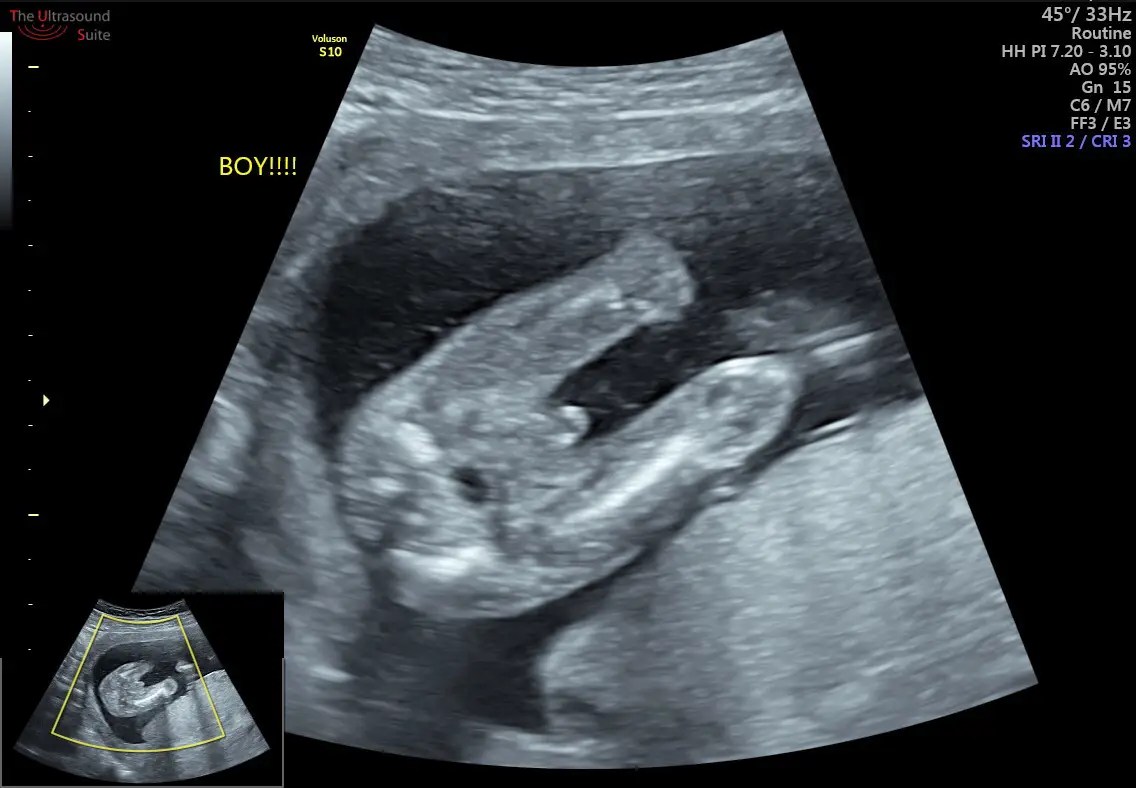

From theultrasoundsuite.ie

How Early Can I Find Out my Baby's Gender? How To Find Out Baby S Gender At Home You can find out whether you’re having a boy or a girl through an ultrasound performed about halfway through your pregnancy, while certain tests that check for chromosomal abnormalities. Find out all about ultrasound testing, genetic testing, and the ramzi method in our article. The earliest way to find out your baby's sex is noninvasive prenatal testing (nipt), a blood. How To Find Out Baby S Gender At Home.